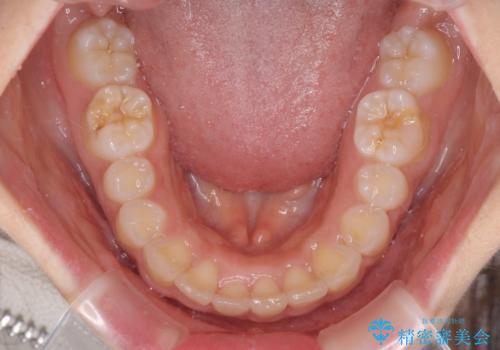

- 飛び出した前歯と全体的なデコボコを気にして来院された患者様です。

上下歯列全体を後方に移動させるため、親知らずは全て抜歯することにしました。